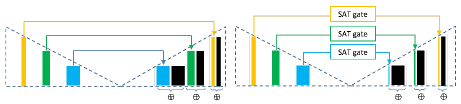

In this paper, we propose a modification of the traditional skip connections, using a novel select-attend-transfer gate, which aims at simultaneously improving segmentation accuracy and reducing memory usage and network parameters (Fig. 1). We focus on skip connections in encoder-decoder architectures (i.e. as opposed to skip connections in residual networks) designed for segmentation tasks. Our proposed select-attend-transfer gate favours sparse feature representations and uses this property to select and attend to the most discriminative feature channels and spatial regions within a skip connection. Specifically, we first learn to identify the most discriminative feature maps in a skip connection, using a set of trainable weights under sparsity constraint. Then, we reduce the feature maps to a single channel using a convolutional filter followed by an attention layer to identify salient spatial locations within the produced feature map. This compact representation forms the final feature map of the skip connection.

We further test the proposed SAT gate on The One Hundred Layers Tiramisu network [24]. Note that we apply the proposed SAT gate to more skip connections in this network i.e. both long skip connections between the encoder and decoder (similar to Figure 1) and the long skip connections inside of each dense block (Figure 4). While our proposed SAT gate reduces the number of parameters in the original Tiramisu network (Table 3) by , it improves Dice results (Table 2) by 3.7% and 2.5% for MRI and skin datasets, respectively.